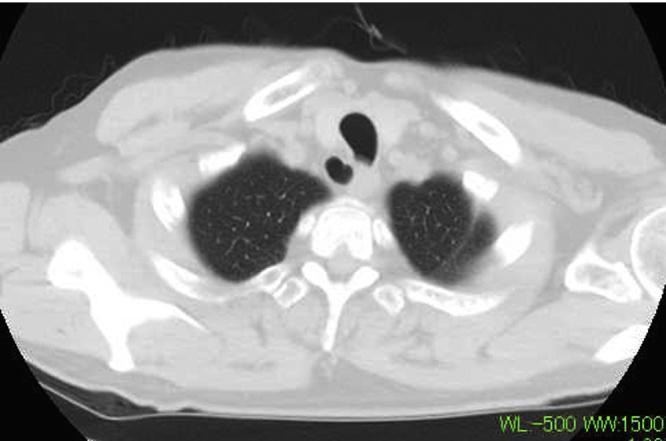

A 65-year-old Japanese nonsmoker man presented with a fever, lower neck pain, and the aggravation of dyspnea for a week. An enhanced computed tomography scan demonstrated that the trachea was displaced by a paratracheal mass with a well-defined thin wall. His respiratory status was so urgent that emergency intubation and surgical drainage of the abscess were performed. A computed tomography scan performed 4days after admission demonstrated shrinking of the abscess, and he was extubated and discharged 7days after admission without any complications.

一名65岁的日本男性非吸烟者,出现发热、下颈部疼痛和呼吸困难加重一周。增强计算机断层扫描显示,气管被一个薄壁清晰的气管旁肿块推移。他的呼吸状况非常紧急,因此进行了紧急插管和脓肿手术引流。入院4天后进行的计算机断层扫描显示脓肿缩小,他在入院7天后拔管出院,无任何并发症。